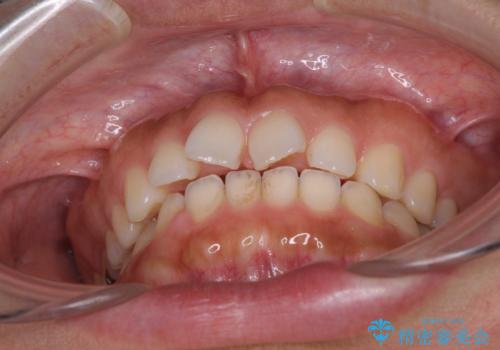

隙間の空いた前歯を閉じたい インビザライン矯正

- 前歯の隙間を気にして来院された患者様です。

隙間、捻転ともに軽微でありましたが、下顎前歯の突き上げにより隙間ができていたため、インビザラインを用いて咬み合わせを改善しながら前歯の歯列を整えていくこととしました。